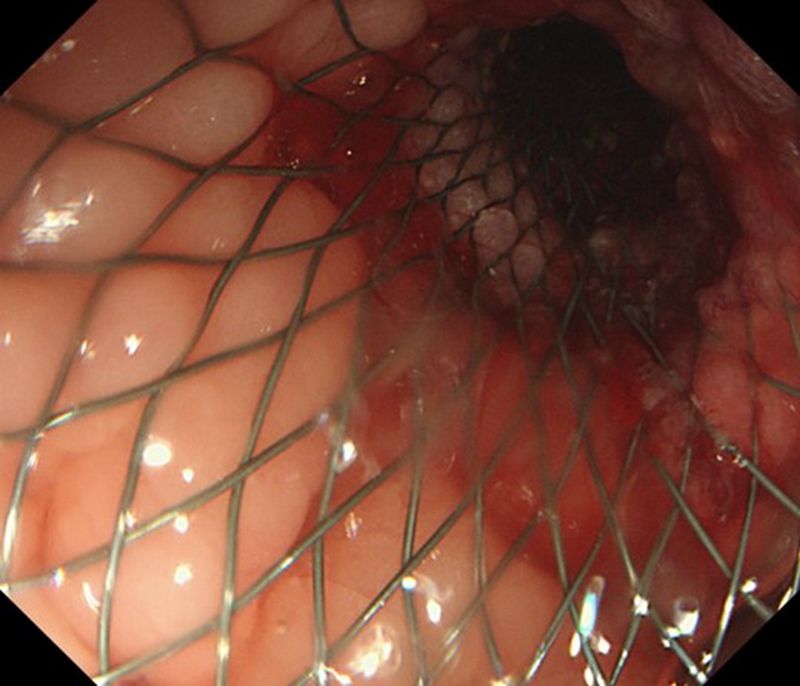

2.DSA下支架植入

开展DSA下食道支架植入术、十二指肠支架植入术、肠道支架植入术、食道气管瘘食道覆膜支架植入封堵术等等。